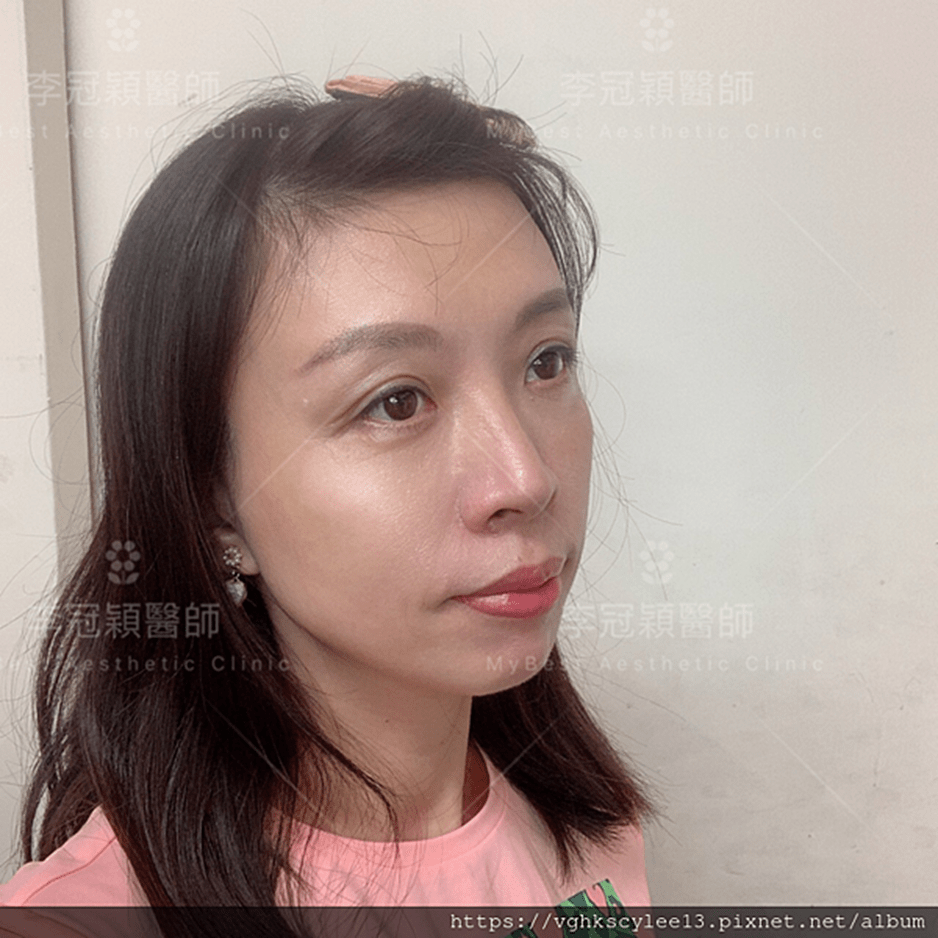

前 後(三個月)太陽穴到側額凹陷,眼尾下垂。(太陽穴不對稱往往來自顴骨大小不對稱)可以調整改善對稱性。

臉型不對稱 在太陽穴有一定落差,上圖經過太陽穴墊片矯正後,也明顯改善不對稱的視覺效果。重要的一點可以支撐眼尾下垂,改善老態眼神!(上圖)經內視鏡墊太陽穴跟提眼尾術後滿意。

(下圖)凹陷太陽穴,提前老態與眼尾下垂,經李醫師內視鏡太陽穴墊片支撐眼尾,幾乎不鬆垂完全抗老。

下圖:太陽穴墊片後兩年,眼尾支撐效果持久。